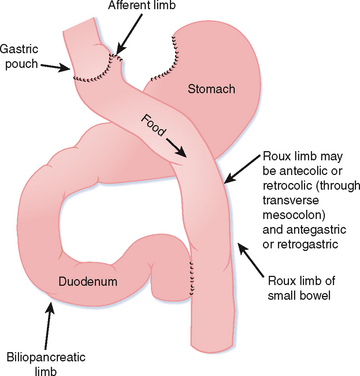

Фотографии медицинских исследований инсулиномы и синдрома Триады Уиппла